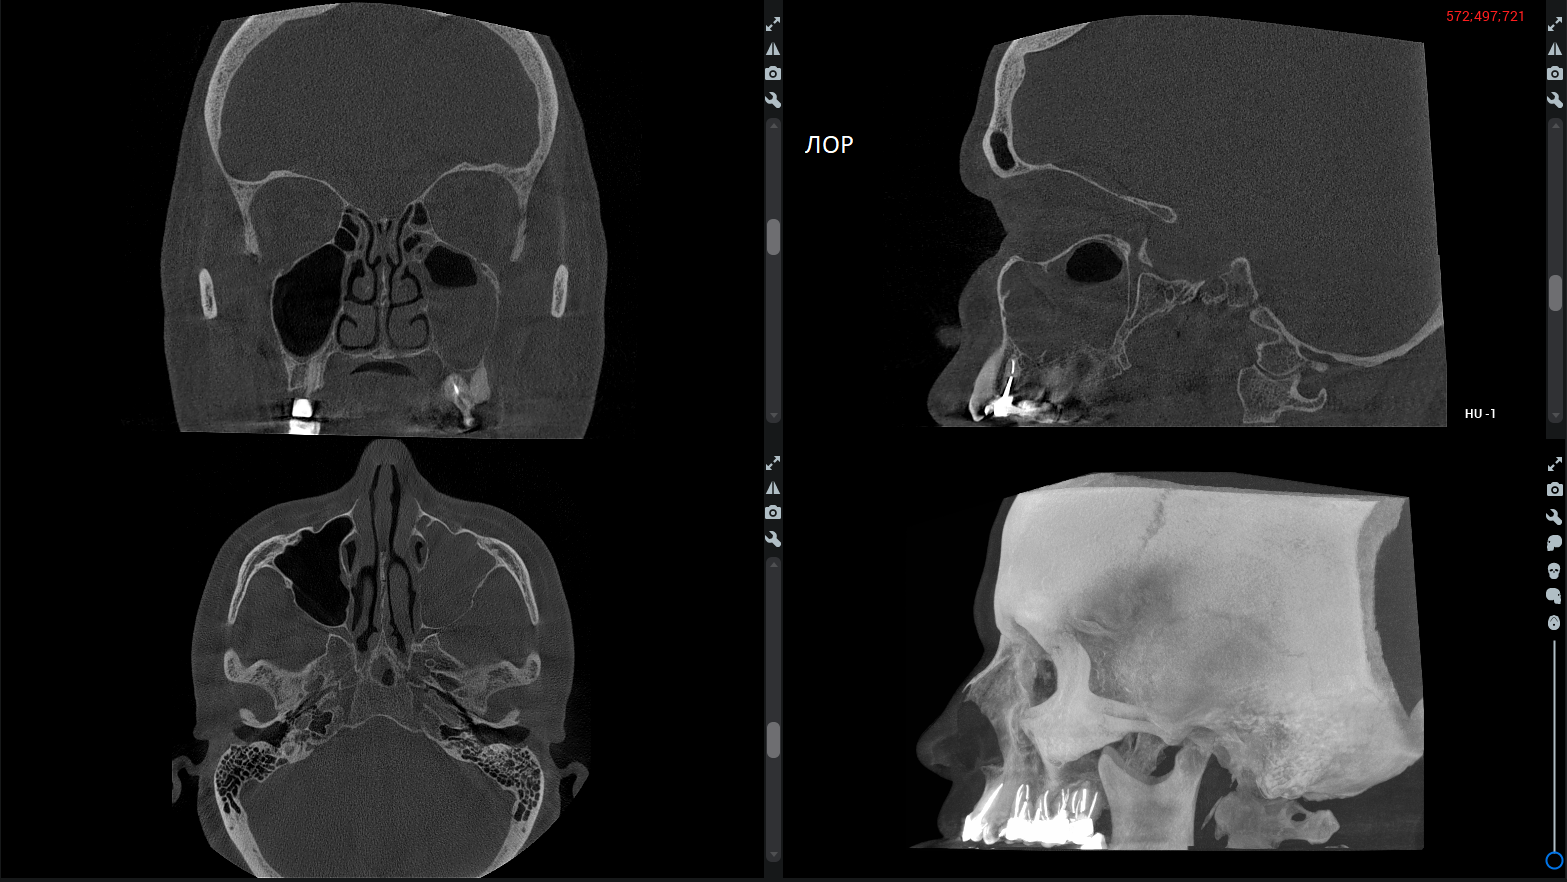

ЛОР-снимки

Связь ЛОР-болезней и заболеваний зубов верхней челюсти – частое явление (например, периодонтит – воспаление тканей вокруг зуба – может осложняться гайморитом). Поэтому на современном ЛОР-снимке и придаточные пазухи носа, и все ткани зубов верхней челюсти должны быть видны идеально.